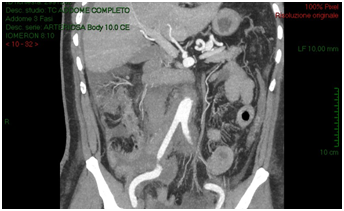

The CT-scan, targeted to a suspect of hemorrhage, did not have delayed phases. Patient received paracentesis with around 3200 cc fluid drained that was sent to microbiological examination. Result of bacteriological exam revealed infection by Proteus Mirabilis and he received target antibiotic therapy with resolution of septic status. In XXII post-operative day, for a progressive increase of serum creatinine we decided to perform an Uro-CT scan. The exam showed reduction of intraperitoneal fluid, right iliac side fluid collection with contrast enhancement during delayed phases; right ureter was not visible under fluid collection (Figure 3). We attempted to insert a ureteral stent in retrograde way but ureter resulted totally interrupted inside the fluid collection so the patient was undergone to explorative laparotomy and toilette of fluid collections. We found ureteral loss of substance of around 3 centimeter localized in anterior ureteral wall. We manufactured end-to-end ureteral anastomosis after positioning of ureteral stent seven French. We removed ureteral stent after 3 months and currently the patient is in follow-up with a good renal function as shown at last CT-scan after 10 months (Figure 4).

Figure 3: Post paracentesis Uro-CT scan showing reduction of intraperitoneal fluid, right iliac side fluid collection with contrast enhancement during delayed phases; right ureter was not visible under fluid collection.